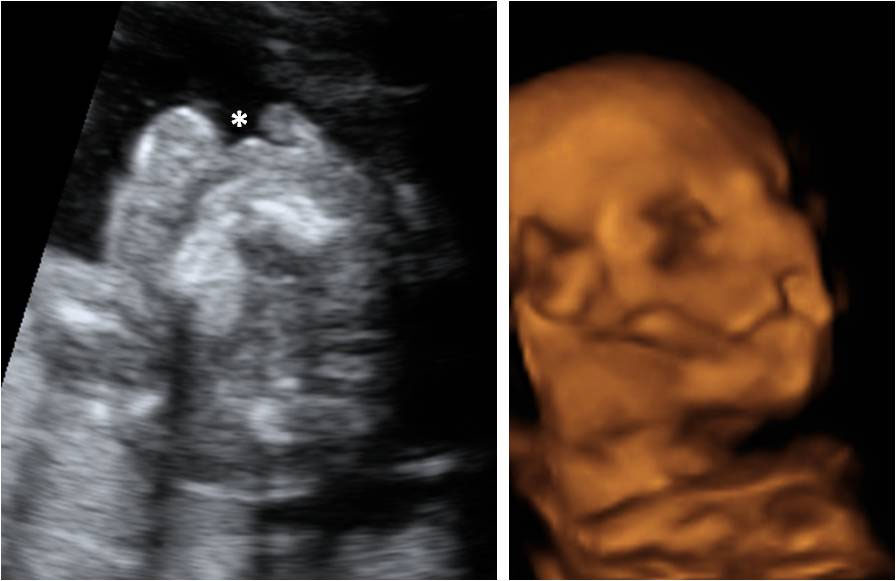

Ecografía Embarazo 2D y 3D Semana 20 - MALFORMACIONES FETALES

Ecografía Embarazo 4D Semana 20 - MALFORMACIONES FETALES